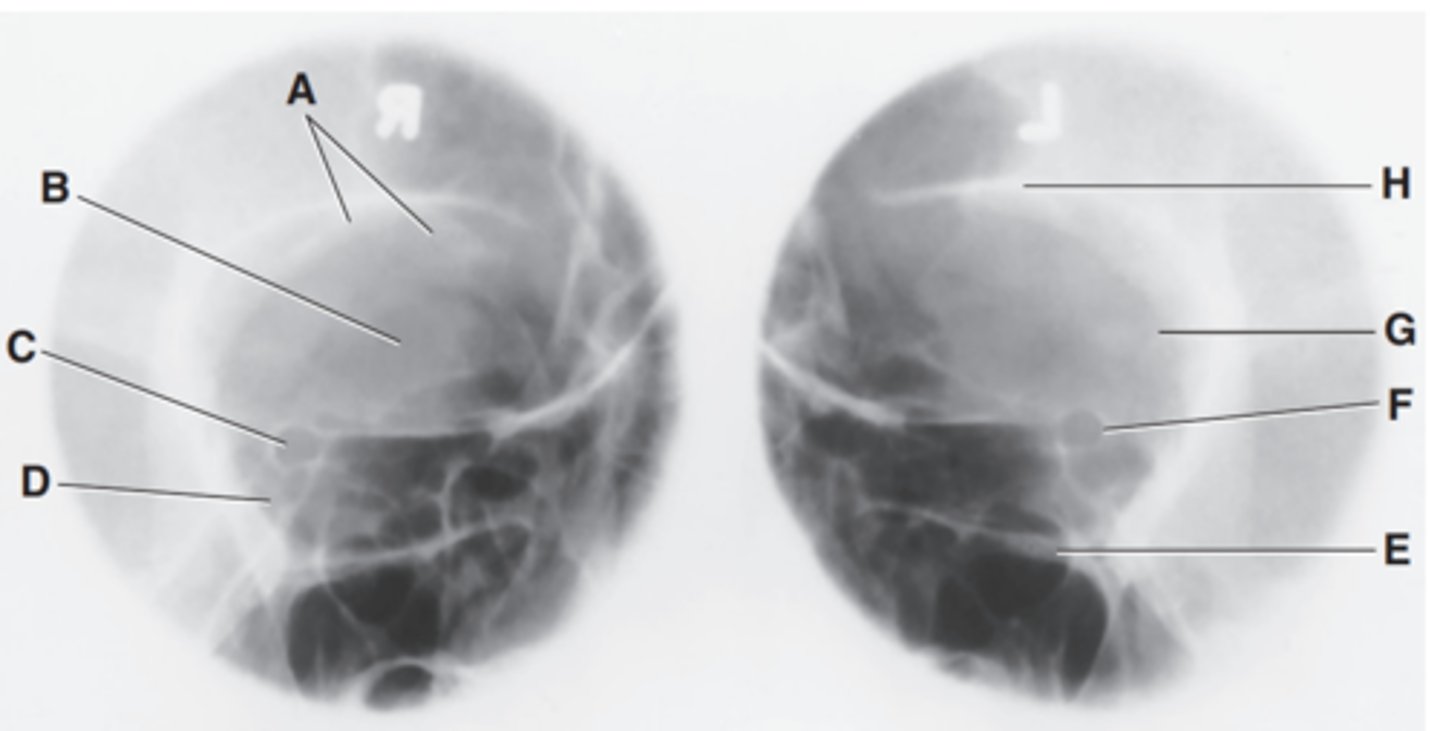

Label A

Mastoid portion of temporal bone

Label B

Occipital bone

Label C

Lambdoidal suture

Label D

Clivus

Label E

Dorsum sellae

Label F

Posterior clinoid processes

Label G

Anterior clinoid processes

Label H

Vertex of cranium

Label I

Coronal suture

Label J

Frontal bone

Label K

Orbital plates

label L

Cribriform plate

Label M

Sella turcica

Label N

Body of sphenoid (sphenoid sinus)

Label O

Petrous portion of temporal bone

Label P